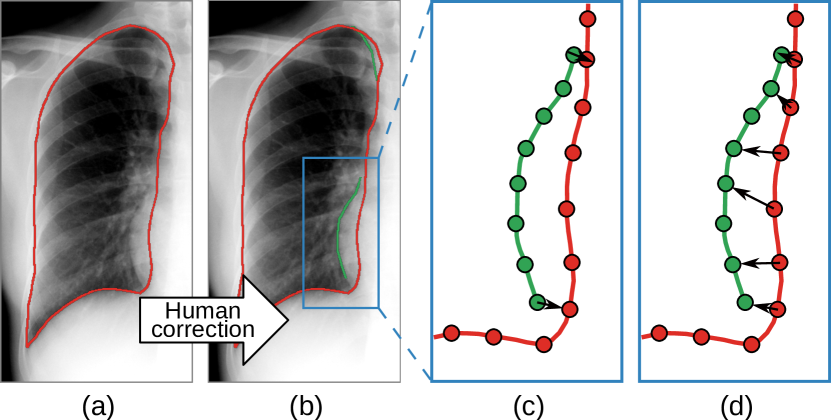

Refer to caption

Fig. 4: Human-in-the-loop. Given a red predicted contour (a), the annotator corrects its wrong parts with green curves (b). For each corrected contour segment, we find two points in the predicted contour, closest to its start and end (c), then each predicted point between the two points are assigned to the closest corrected point (d). This prevents the point correspondence to be scattered.

2.4 Human-in-the-loop

Learning from one exemplar is based on the assumption that the anatomical structure has similar boundary features in all images. It works in most cases, but outliers are inevitable. To achieve even higher accuracy in testing, sometimes we need to consider more possibilities in training. To this end, the proposed CTN offers a natural way to incorporate additional labeled images with a human-in-the-loop mechanism.

Assuming a CTN model is trained with one exemplar, we want to finetune it with more segmentation annotations. We first run this model on a set of unlabeled images and select a number of images with wrong predictions as new samples. Instead of drawing the whole contour from scratch on these new images, the annotator only needs to draw some partial contours, in order to correct the wrong prediction (as shown in Fig. 4(b). The point-wise training of CTN makes it possible to learn from these partial corrections. This way, we reduce the labor cost to the minimum.

A partial contour matching loss is proposed to utilize the partial ground truth contours during the CTN training. Denote 𝐂^^𝐂\hat{\mathbf{C}} as a set of partial contours in image I𝐼I, each element of which is an individual contour segment. For each contour segment C^i𝐂^subscript^𝐶𝑖^𝐂\hat{C}_{i}\in\hat{\mathbf{C}}, we build the point correspondence between C^isubscript^𝐶𝑖\hat{C}_{i} and C𝐶C. For each C^isubscript^𝐶𝑖\hat{C}_{i}, we find two points in the predicted contour C𝐶C that are closest to the start and end points of C^isubscript^𝐶𝑖\hat{C}_{i}, then each predicted point between the two points are assigned to the closest corrected point. Denote the corresponding predicted contour segment by Cisubscript𝐶𝑖C_{i} (CiCsubscript𝐶𝑖𝐶C_{i}\in C). We define the distance between C𝐶C and C^isubscript^𝐶𝑖\hat{C}_{i} as the Chamfer distance from Cisubscript𝐶𝑖C_{i} to C^isubscript^𝐶𝑖\hat{C}_{i}:

3.3 Incorporating human corrections

In this section, we validate the effectiveness of the proposed human-in-the-loop mechanism by simulating manual corrections of wrong segmentation by an annotator. Specifically, we assume that the annotator tends to correct more severe errors with higher priority. To simulate this behavior, we first segment the unlabeled training images using the one-shot trained model and calculate their HD to the ground-truth segmentation (which is not used in training). Then, we select the worst n%percent𝑛n\% images as candidates for correction. For each predicted contour in these images, we calculate its point-wise L2 distances to the ground-truth and mark vertices with distances larger than 3 pixels as errors. We group consecutive error vertices into segments and use the corresponding ground-truth vertices as corrections. Under this setting, we conduct human-in-the-loop training using corrections of 10%, 25% and 100% training images, respectively.

Fig. 7 shows the performances of the original one-shot model and three human-in-the-loop finetuned models. We observe that our model consistently improves with more corrections. Specifically, using 10% corrections, the mean IoU is improved from 96.58% to 97.10% and the mean HD is reduced from 8.66 to 7.32, respectively. When using 25% corrections, CTN can outperform DeepLab, (IoUs of 97.38% vs. 97.16%, and HDs of 6.81 vs. 7.25). With corrections on all training samples, CTN further reaches an IoU of 97.52% and a HD of 6.27. We also stress that the effort of our human-in-the-loop correction of unlabeled training samples is significantly lower than annotating them from scratch (as required by fully supervised methods), as only partial corrections are needed. Thus, these results indicate that on all 4 evaluated tasks, CTN with the human-in-the-loop mechanism can achieve superior performance than fully supervised methods and require considerably less annotation effort.